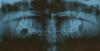

Crystalmindd Опубликовано 11 марта, 2011 Поделиться Опубликовано 11 марта, 2011 (изменено) думаю необходима консультация хирурга-стоматолога для определения адекватности заживления перелома. Похрустывания в области сустава (что перед ухом) могут быть. В области линии перелома хрустеть не должно.Выложите хотя б снимок после шинирования что лиЛадно спасибо вам.Вот снимок через 5 дней после наложения шин.Что Вы думаете?и в каких случаях было бы оправдано удаление 47 зуба?так , как я подозреваю, что врач удалил его по ошибке. Кусок трещины на снимке, закрывает подпись, вот еще на всякий случай выложил снимокhttp://s2.ipicture.ru/uploads/20110311/RCv61UEa.jpg Изменено 11 марта, 2011 пользователем Crystalmindd Ссылка на комментарий

ПалСаныч Опубликовано 12 марта, 2011 Поделиться Опубликовано 12 марта, 2011 (изменено) 47 зуб следовало бы удалить, если через него проходит линия перелома (по качеству снимка сложно точно сказать, но вроде как верхний край проходит через лунку 47, соответственно в полости рта мог быть разрыв десны рядом с зубом). Либо если 47 зуб был разрушен либо травмой, либо кариесом. Но сейчас об этом мы сказать не можем. При таком положении после шинирования, как на снимке, я бы не стал делать еще один снимок перед снятием шин, так как отломки стоят хорошо. На консультацию по поводу хруста ходили? Изменено 12 марта, 2011 пользователем ПалСаныч Ссылка на комментарий